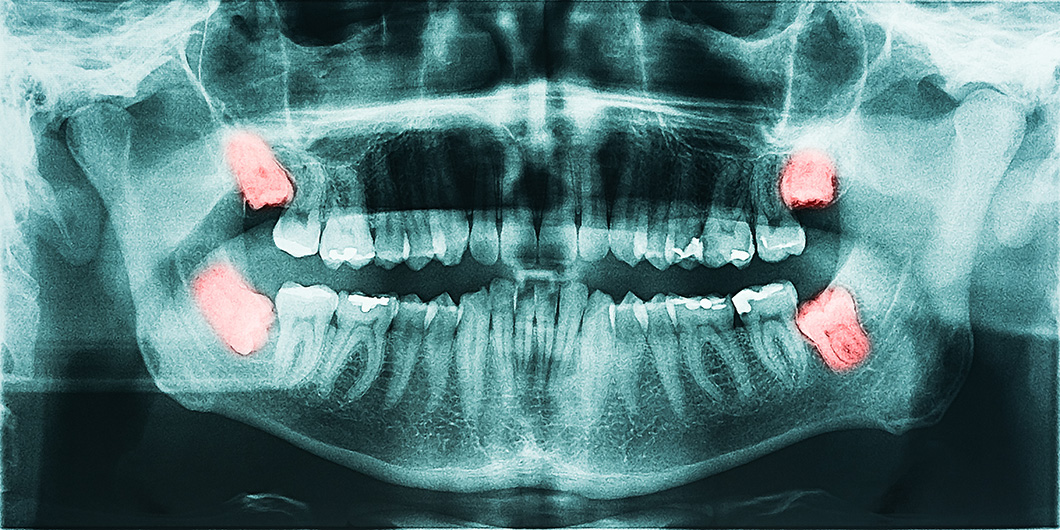

Tooth Extractions in Los Angeles

Sometimes it is necessary to extract a tooth. This can happen for a variety of reasons. Extractions are commonly performed in cases where a deciduous “baby” tooth is reluctant to fall out, a severely broken down and non-restorable tooth is present, or “wisdom tooth” is poorly positioned and unable to fully erupt into place.

Pano xray